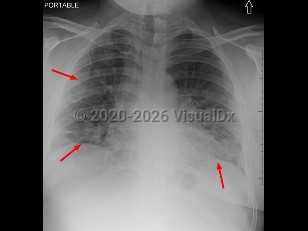

Clinical features primarily include fever and upper respiratory tract symptoms with rhinorrhea, congestion, and pharyngitis that can progress to include symptoms of lower respiratory tract illness (eg, cough, shortness of breath), although many patients also report associated gastrointestinal complaints (nausea, vomiting). Reported cases have ranged from asymptomatic to severe; the case fatality rate varies worldwide, ranging from 0.1%-4.9% based on data compiled by Johns Hopkins. Clinical presentation can vary significantly, particularly with respect to vaccination and boosting status and time from last COVID infection.

- Severe (dyspnea, hypoxia, or > 50% lung involvement on imaging)